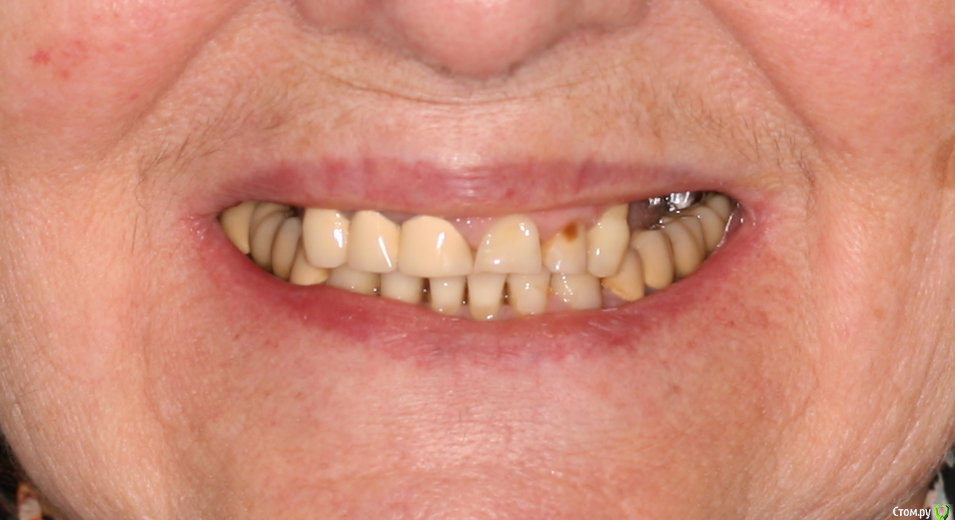

kramer Опубликовано 15 мая, 2019 Поделиться Опубликовано 15 мая, 2019 Коллеги, здравствуйте. Нужен совет. Ситуация: пациентка 70 лет (родственница), давно носила бюгельный протез, и вот одному из опорных зубов пришел конец. КТ ниже, фотографии завтра добавлю. Рассматриваю вариант изготовления несъемного протеза на 4 имплантатах. Опыта все-на-4 нет. Поэтому хотелось бы по крайней мере собрать информацию, возможна ли такая опция. Особенно волнует 2 момента: 1) Отсутствует вертикальная атрофия альвеолярного отростка во фронтальном отделе. Линия улыбки низкая. Предположим, окончательный протез будет м\к или циркон. Означает ли это, что редукцию кости делать необязательно? (правда там и редуцировать особо некуда). 2) В области 14 и 24 ширина гребня 3,5-4 мм. Что делать с этим? Оставлять пришеечную часть винта не покрытым костью небно или пытаться каким-то образом конденсировать кость? 14122224 Ссылка на комментарий